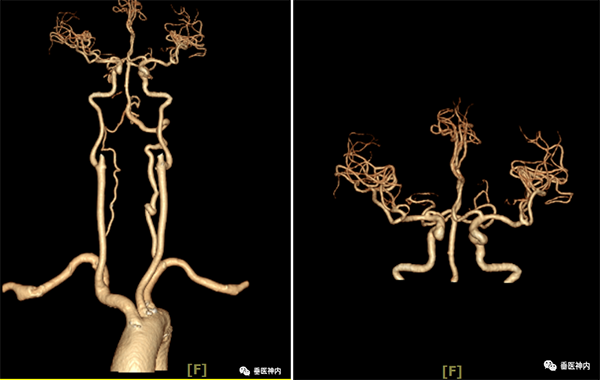

四、CTA和CTP

是一种介入检测方法,原理是显影剂被注入到血管里,因为X光穿不透显影剂,从而可显示出血管影像。CT血管成像(CTA)指静脉注射含碘造影剂后,经计算机对图像进行后处理,可以同时显示血管及骨性结构,清晰显示三维颅内血管系统,对狭窄或闭塞血管可提供重要的诊断依据。